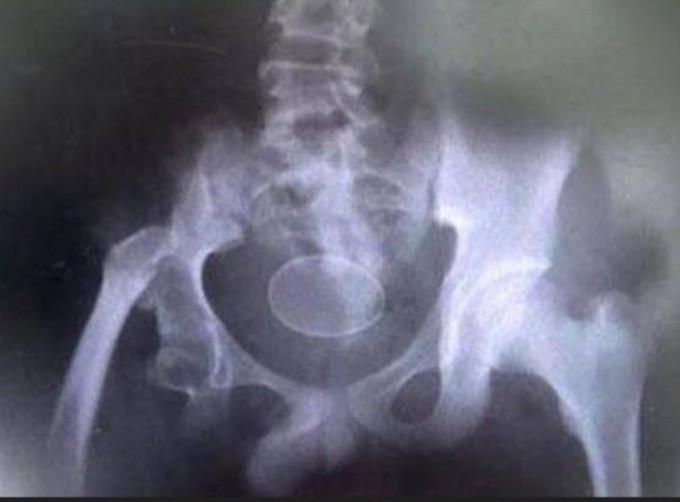

O garoto tinha dificuldade em andar quando chegou ao local e os médicos afirmaram ser impossível um humano colocar um ovo, mas a família de Akmal tinha um raio-x para comprovar a história.